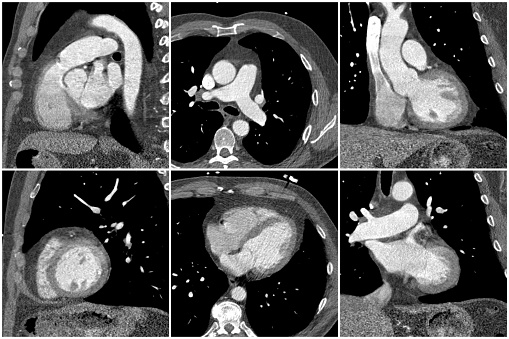

Recurrent kidney stone patients are at a higher risk of heart disease and osteoporosis. The findings suggest that close monitoring of recurring kidney stones could help protect patients from heart-related problems. Nearly 10 percent of men and seven percent of women will develop kidney stones, and over the last few decades mounting evidence has shown ...click here to read more